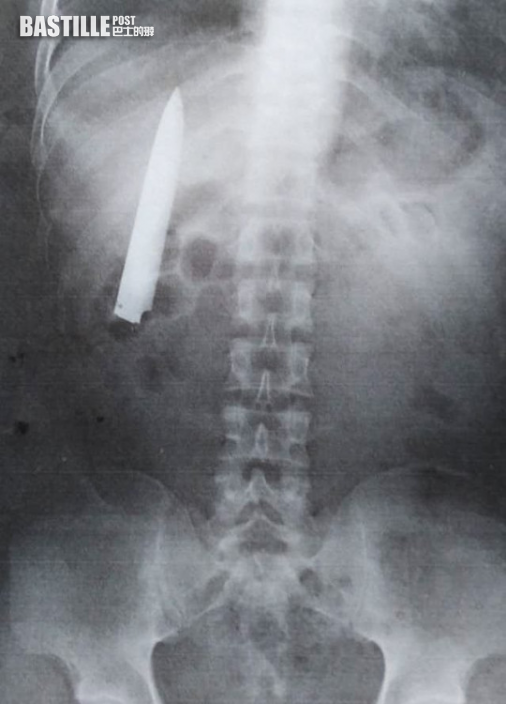

居於菲律賓哥打巴托省基達帕萬市(Kidapawan City)的25歲男子Kent Ryan Tomao,日前到當地一間採礦公司應徵,被公司要求到南阿古桑省一家醫院進行身體檢查,卻在X光檢查過程中,發現其右側腹位置埋了一把4吋長(約10厘米)的刀刃。

Tomao照X光時發現胸口埋有利刀已達14個月。(網上圖片)

利刀位置靠近肺部。(網上圖片)

Tomao稱他一直不知道胸口有刀,但該位置間中會有痛感,尤其天氣寒冷時會特別疼痛,但他都未有理會。現時院方認為他必須盡快接受手術取出刀刃,因其位置很靠近肺部,情況非常危險。但Tomao沒有足夠資金,只好向當地電台求助,希望有人可以伸出援手。